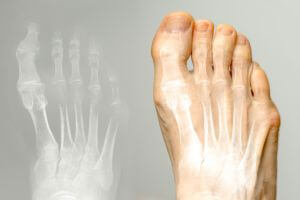

内反小趾(ないはんしょうし)とは、足の小指が内側(親指側)に曲がって変形する症状です。

小指の付け根の骨が外側に飛び出し、靴に当たって赤く腫れたり、タコや痛みが出たりするケースもあります。

病院では主に「レントゲン検査」や「視診・触診」を通じて診断が行われます。

小指の曲がり具合(内反角度)や、関節の変形、骨の並び方などを確認し、変形の進行度や炎症の有無を見極めます。